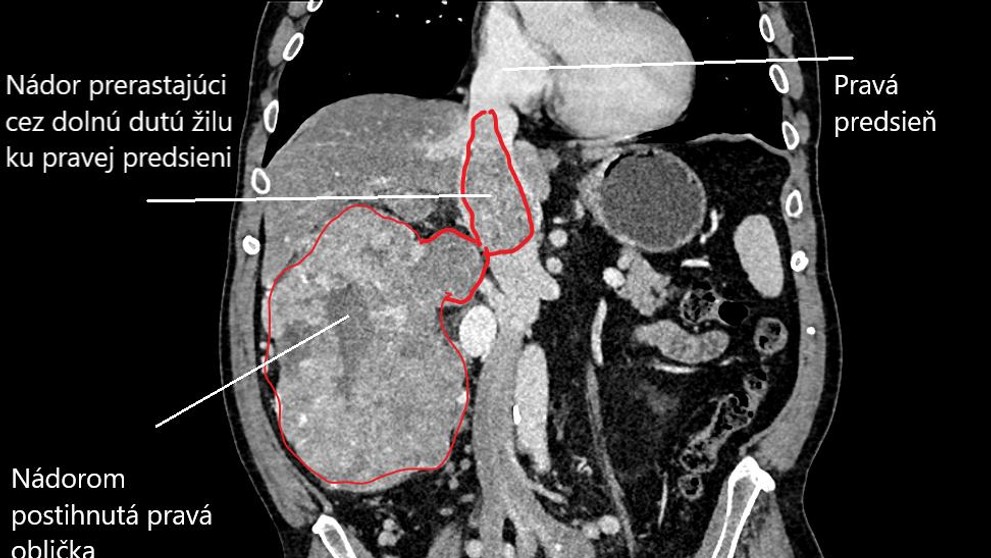

Cievni chirurgovia v Rooseveltovej nemocnici v Banskej Bystrici vyoperovali pacientovi z brušnej dutiny nádor vo veľkosti rugbyovej lopty. Zložitý zákrok urobili v uplynulých dňoch a pacienta tým zbavili priameho ohrozenia na živote. Informovala o tom nemocnica na sociálnej sieti.

„Operácia, ktorú vykonali odborníci z kliniky transplantačnej chirurgie pod vedením zástupcu prednostu Radoslava Kminiaka, bola výnimočná. Nádor vyrastal z obličky, zasahoval dolnú dutú žilu a pravú predsieň srdca. Vyoperovať nádor prechádzajúci najväčšou žilou v tele a následne zabezpečiť jej ďalšiu funkčnosť si vyžaduje dlhé roky praxe v cievnej chirurgii,“ zdôraznila nemocnica.

Ako dodala, vzhľadom na vysokú náročnosť výkonu sú pacienti s takto rozsiahlym typom nádoru odosielaní do rúk ich chirurgov z celého Slovenska.